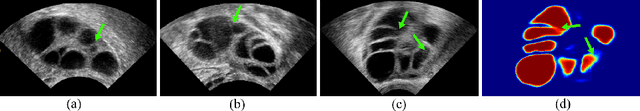

Abstract:Ultrasound (US) imaging is widely used for anatomical structure inspection in clinical diagnosis. The training of new sonographers and deep learning based algorithms for US image analysis usually requires a large amount of data. However, obtaining and labeling large-scale US imaging data are not easy tasks, especially for diseases with low incidence. Realistic US image synthesis can alleviate this problem to a great extent. In this paper, we propose a generative adversarial network (GAN) based image synthesis framework. Our main contributions include: 1) we present the first work that can synthesize realistic B-mode US images with high-resolution and customized texture editing features; 2) to enhance structural details of generated images, we propose to introduce auxiliary sketch guidance into a conditional GAN. We superpose the edge sketch onto the object mask and use the composite mask as the network input; 3) to generate high-resolution US images, we adopt a progressive training strategy to gradually generate high-resolution images from low-resolution images. In addition, a feature loss is proposed to minimize the difference of high-level features between the generated and real images, which further improves the quality of generated images; 4) the proposed US image synthesis method is quite universal and can also be generalized to the US images of other anatomical structures besides the three ones tested in our study (lung, hip joint, and ovary); 5) extensive experiments on three large US image datasets are conducted to validate our method. Ablation studies, customized texture editing, user studies, and segmentation tests demonstrate promising results of our method in synthesizing realistic US images.

Abstract:Ultrasound (US) is widely accepted in clinic for anatomical structure inspection. However, lacking in resources to practice US scan, novices often struggle to learn the operation skills. Also, in the deep learning era, automated US image analysis is limited by the lack of annotated samples. Efficiently synthesizing realistic, editable and high resolution US images can solve the problems. The task is challenging and previous methods can only partially complete it. In this paper, we devise a new framework for US image synthesis. Particularly, we firstly adopt a sketch generative adversarial networks (Sgan) to introduce background sketch upon object mask in a conditioned generative adversarial network. With enriched sketch cues, Sgan can generate realistic US images with editable and fine-grained structure details. Although effective, Sgan is hard to generate high resolution US images. To achieve this, we further implant the Sgan into a progressive growing scheme (PGSgan). By smoothly growing both generator and discriminator, PGSgan can gradually synthesize US images from low to high resolution. By synthesizing ovary and follicle US images, our extensive perceptual evaluation, user study and segmentation results prove the promising efficacy and efficiency of the proposed PGSgan.